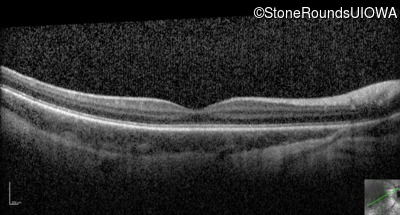

Optical Coherence Tomography - Right - 10/125 +2

Exemplar / OCT Stack

OCT Stack